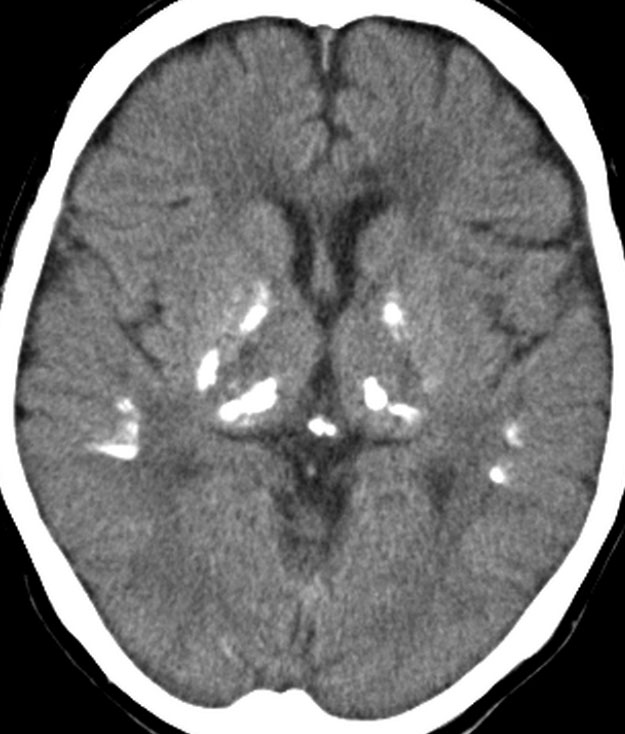

全脳照射後の脳内石灰化(幼児例)

20年以上前のことですが,髄芽腫の1歳6ヶ月の子どもに25グレイの全脳照射をしました。これは15年後のCTです。

脳の萎縮は目立ちません。認知機能は低いのですが支援を受けて学校へ行けています。下垂体機能は低下して成長ホルモンなどの補充をして普通に暮らせています。

CTで,両側の大脳基底核(被殻と淡蒼球)と視床後部に石灰化がみられます。乳幼児期に放射線治療を受けた子どもに見られるものです。